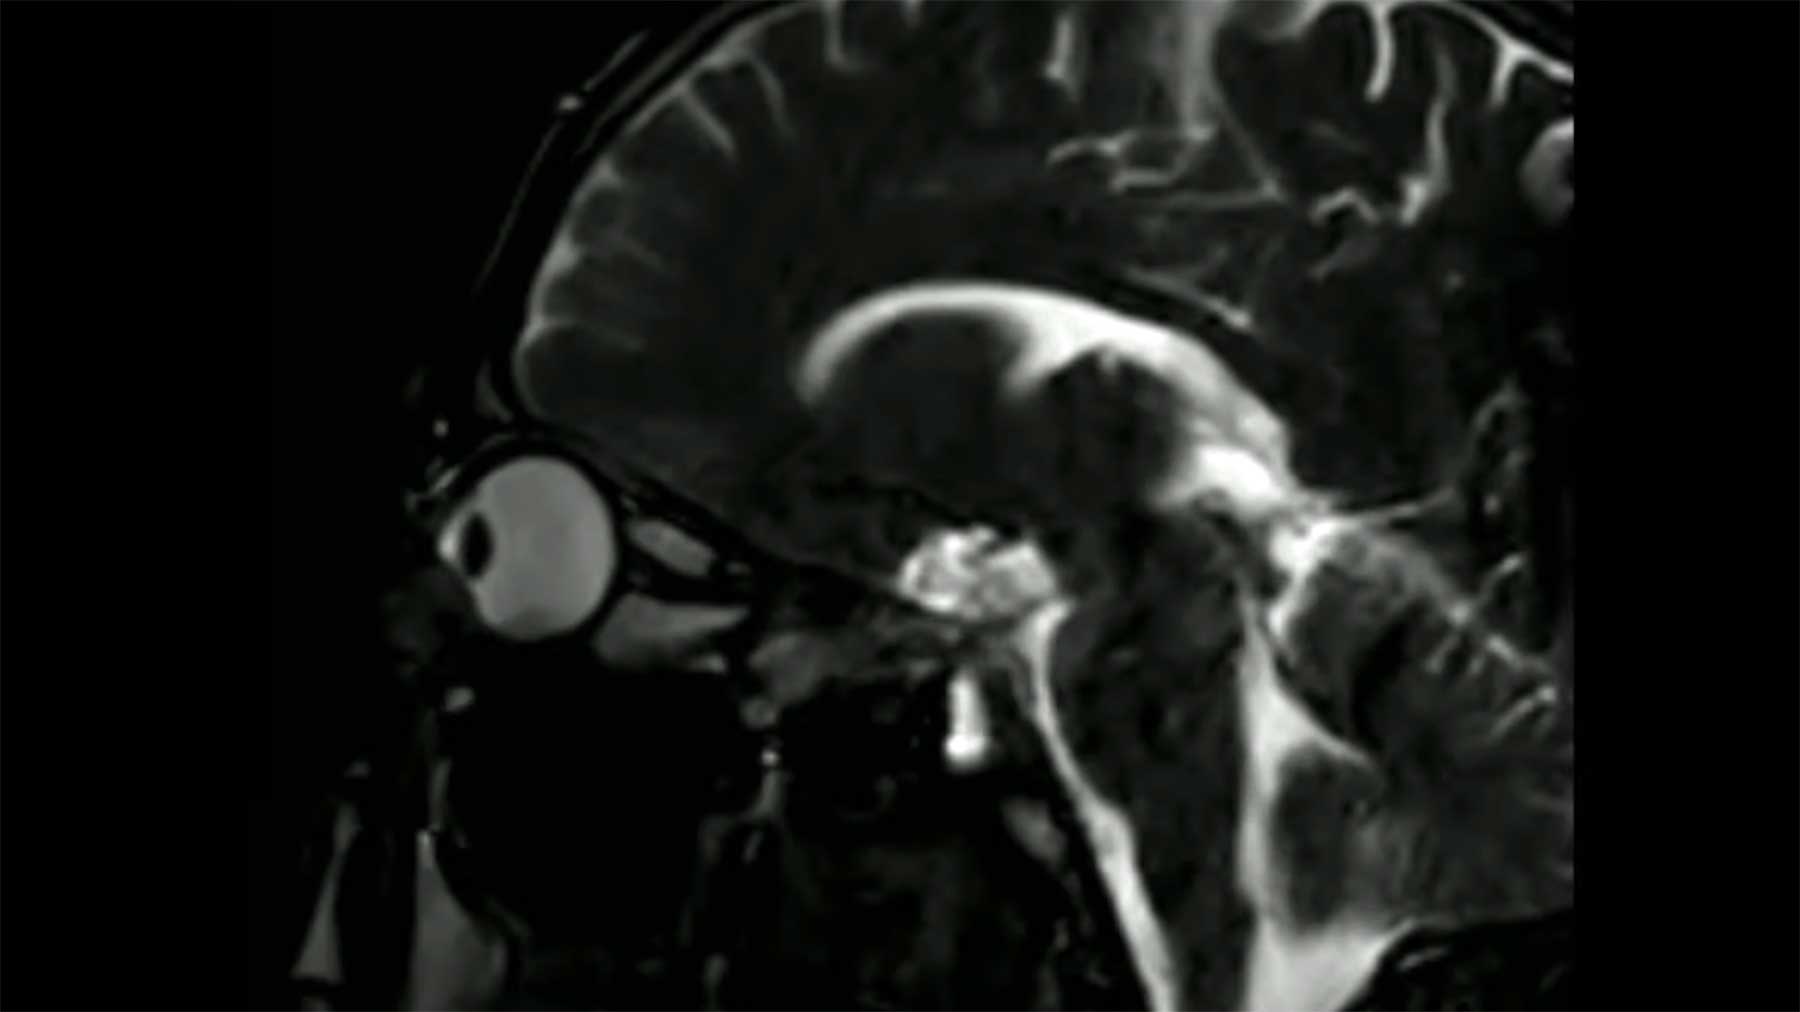

Unser Körper steckt voller vermeintlicher Stabilität, die eigentlich gar nicht so da ist. Wir bekommen nur nicht wirklich mit, was da im Inneren unseres Körpers zu sich geht. Was abgefangen wird, wie von Stoßdämpfern oder Knautsch-Zonen am Auto. Augenreiben, zum Beispiel – klar, da wird ein bisschen am Auge gedrückt, aber dass da so weitreichende Bewegungen im Kopf stattfinden, wie diese Magnetresonanzaufnahmen zeigen, die Damien Gatinel hochgeladen hat, hätte ich nicht vermutet. Beim nächsten Mal werde ich etwas vorsichtiger den Schlaf aus den Augen reiben…

„For the first time, dynamic MRI objectivates the effect of eye rubbing on the cornea and adjacent orbital structures. This material provides another evidence that keratoconus (and possibly other ocular conditions) is caused by excessive eye rubbing.“